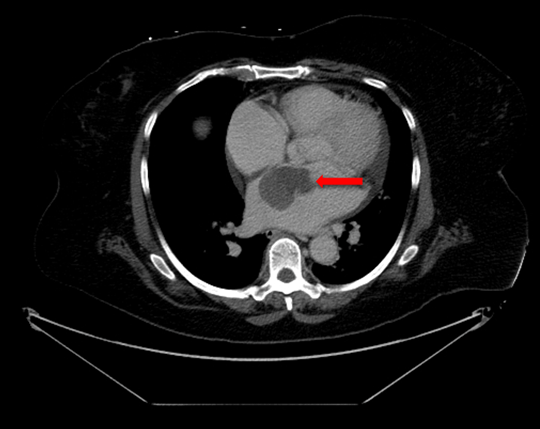

Rate control was achieved with diltiazem infusion and anticoagulation with intravenous heparin was initiated. Echocardiogram showed a left atrial mass adjacent to the interatrial septum suspicious for atrial myxoma (Figure 1). Computed tomography scan showed a left atrial filling defect that enhanced with contrast and measured 4.5x3.3x4.4 cm (Figure 2) as well as a filling defect in the superior mesenteric artery (Figure 3). Lower extremity angiogram demonstrated abrupt cessation of flow consistent with an embolus to the right popliteal artery (Figure 4) and a patent left popliteal artery. Right popliteal arterial thrombectomy was performed. The patient then underwent excision of the left atrial mass. Maze procedure and left atrial appendage ligation. The examination of excised mass revealed an organized thrombus (Figure 5). The postoperative course was uneventful and the patient was discharged on warfarin and metoprolol.

Figure 1: Echocardiogram demonstrating left atrial mass (arrow).

Abbreviations: LA Left Atrium, LV Left Ventricle.